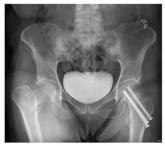

A 20-year-old man presents following a motor vehicle collision in which the car he was driving was broadsided by another vehicle. His air bag deployed...